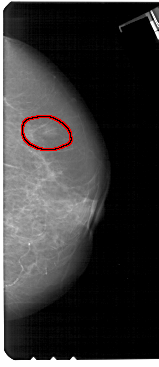

FILE: A_1357_1.RIGHT_CC.OVERLAY

TOTAL_ABNORMALITIES 1

ABNORMALITY 1

LESION_TYPE MASS SHAPE OVAL MARGINS ILL_DEFINED

ASSESSMENT 4

SUBTLETY 3

PATHOLOGY BENIGN

TOTAL_OUTLINES 1

BOUNDARY